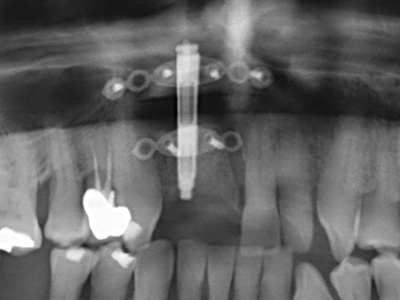

As shown in the past, basically any bone surgery procedure represents a possible indication for piezo surgery. Thus preparation of the mobile segment in distraction osteogenesis (Fig. 23-25) and sandwich osteotomy uses special attachments without endangering the blood supply to the crestal section, which is essential for the success of both techniques (Gonzalez-Garcia, Diniz-Freitas et al. 2008).